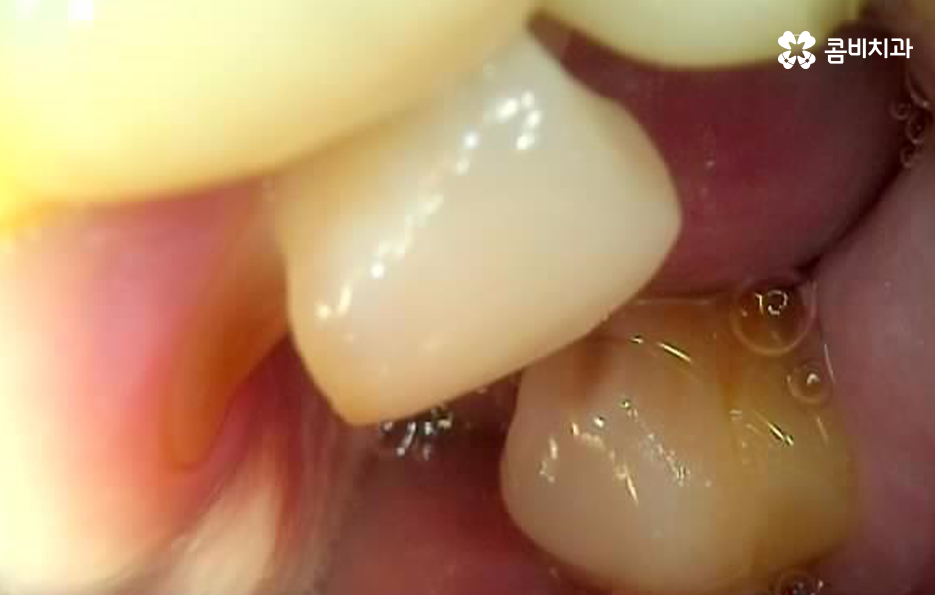

위 사진을 보시면 치아 자체의 노화나 균열도 물론 크지만 잇몸이 내려앉아서 치아의 뿌리 부분이 외부에 노출되어 있는 것을 알 수 있는데요. 노인임플란트 필요로 하는 분들의 치아 상실의 대표적 원인은 충치 부터 오래된 크라운, 치아의 손상 및 균열로 인한 문제도 크겠지만 결정적으로는 치주염으로 인해 잇몸 뼈가 녹고 잇몸 퇴축으로 인한 치아 상실이 노년기에 발생하는 치아 상실의 대표적 원인이 되고 있어요

위 케이스의 노인임플란트 치료의 경우 치아의 균열부터 뿌리까지 깊어진 충치, 치주염 까지 복합적인 이유로 치아를 상실하고 여러 개의 임플란트를 식립한 사례라고 할 수 있는데요. 그래도 아직은 잔존하고 있는 치아가 많기 때문에 이미 상실한 치아에는 노인임플란트 각 위치에 맞게 적절한 치료를 받고 나머지의 자연치아에 대해서는 잘 관리하는 것이 중요한 시점이라 할 수 있어요